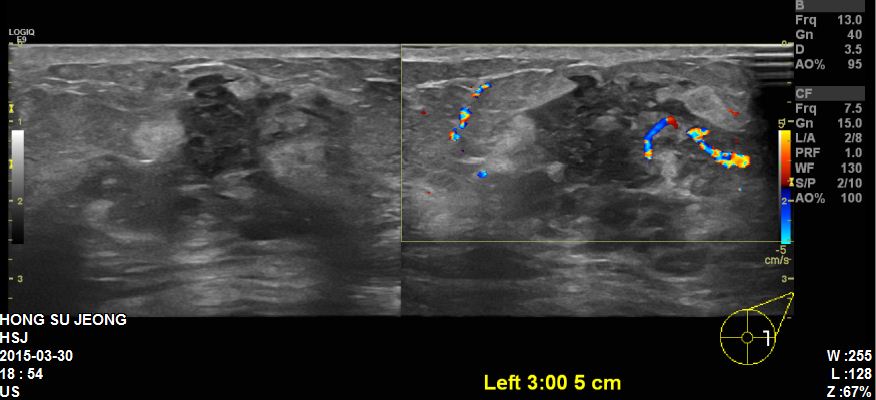

좌측유방에 만져지는 멍우리로 내원하신 70대 환자분이십니다.

본원초음파상 좌측유방에 혹과 겨드랑이에 림프절 비대 확인하였고

각각 조직검사와 세침검사 시행한결과

침윤성유관암 림프절 전이 확인되었습니다.